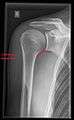

- Transaxillary projection

The arm should be abducted 80 to 100 degrees. This method reveals:[19]

- The horizontal alignment of the humerus head in respect to the socket, and the lateral clavicle in respect to the acromion.

- Lesions of the anterior and posterior socket border or of the tuberculum minus.

- The eventual non-closure of the acromial apophysis.

- The coraco-humeral interval

Transaxillary conventional radiography